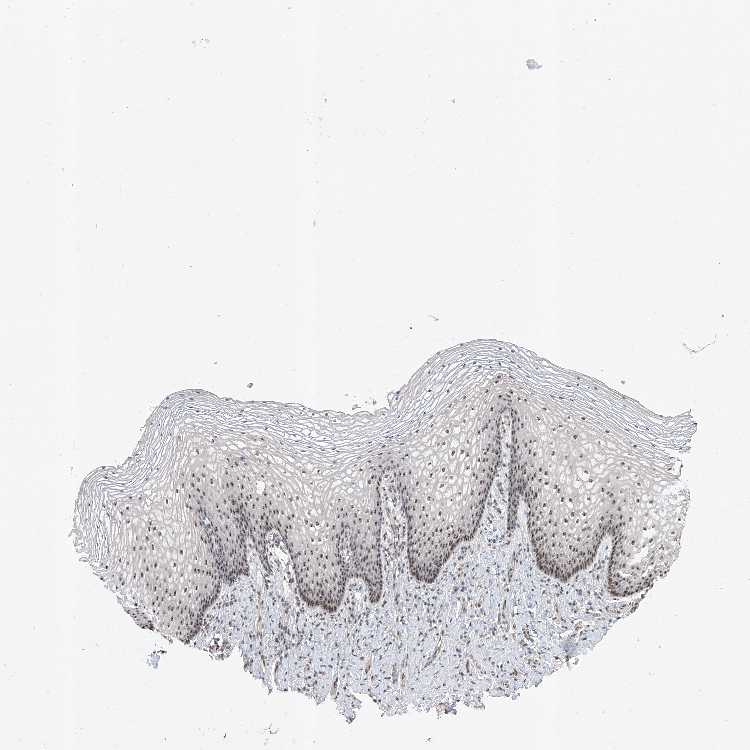

TISSUE PRIMARY DATA VAGINA Show tissue menu

VAGINA - Antibody stainingi

Antibody staining in the annotated cell types in the current human tissue is reported as not detected, low, medium, or high, based on conventional immunohistochemistry profiling in selected tissues. This score is based on the combination of the staining intensity and fraction of stained cells.

Each image is clickable and will lead to virtual microscopy that enables deeper exploration of all samples and also displays staining intensity scores, fraction scores and subcellular localization as well as patient and tissue information for each sample.

Antibody HPA029954Antibody HPA029979Antibody HPA029980

Squamous epithelial cells MediumMediumMedium